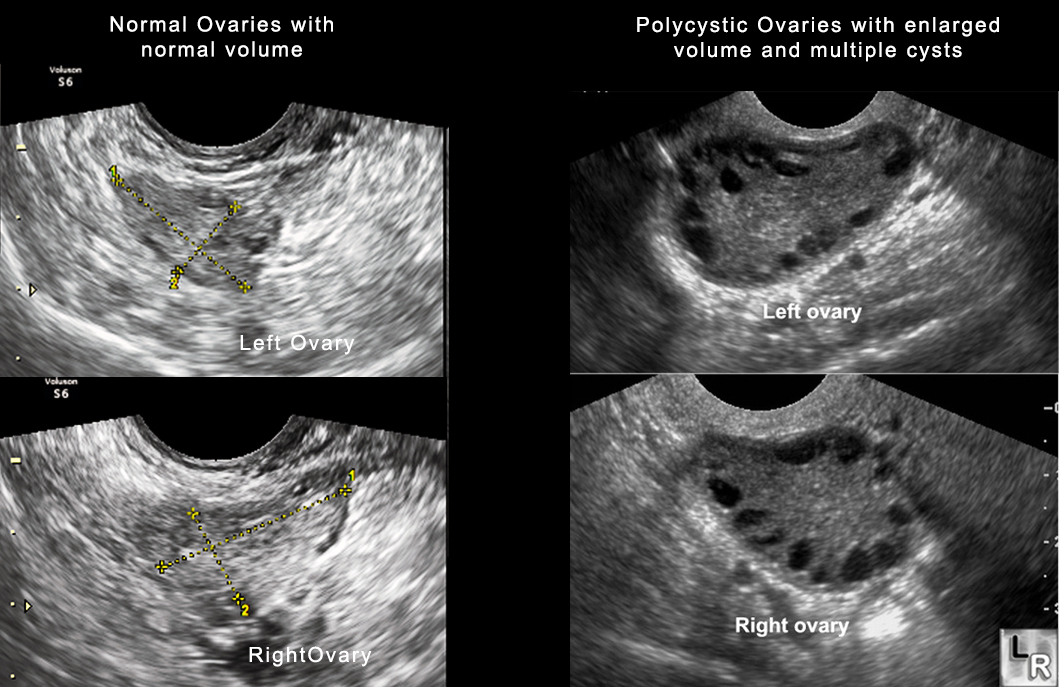

• Polycystic ovaries. Your ovaries might be enlarged and contain follicles that surround the eggs. As a result, the ovaries might fail to function regularly.